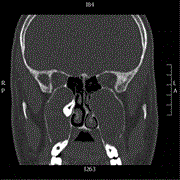

Ectopic maxillary tooth as a cause of recurrent maxillary sinusitis: a case report and review of the literature

Ali Almomen and others

Journal of Surgical Case Reports, Volume 2020, Issue 9, September 2020, rjaa334, https://doi.org/10.1093/jscr/rjaa334